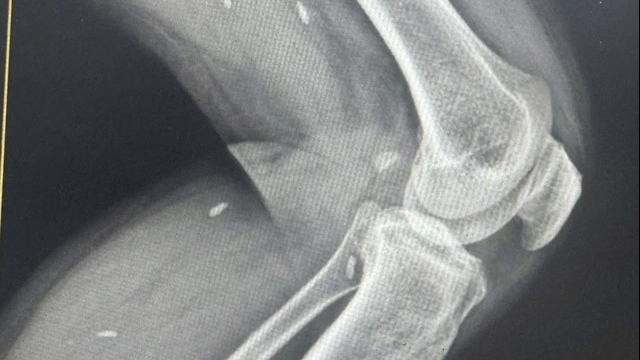

![]() |

| Hình ảnh bác sĩ đang tán sỏi laser niệu quản ngược dòng |